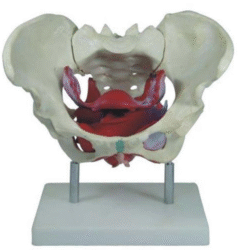

Skeleton Models(human bone, muscle, etc.)